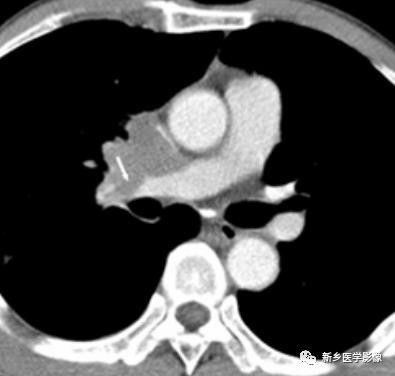

肺动脉内癌栓CT图像

右肺中心性肺癌直接侵犯肺动脉,致肺动脉内癌栓形成(箭示)